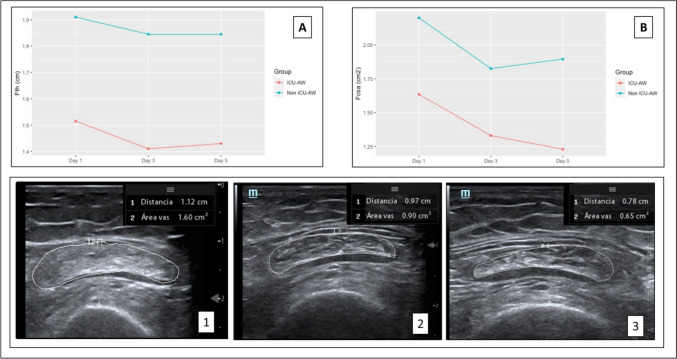

Methods: Forty-three surgical and medical ICU patients underwent serial MUS measurements of the femoral cross-sectional area (Fcsa) and femoral + vastus intermedius thickness (F + VIth) on days 1, 3 and 5 post-ICU admission. Patients were categorized as having ICU-AW (Medical Research Council (MRC) sum score < 48 at discharge) or not. Univariate and multivariate logistic regression analyses were performed to identify predictors of ICU-AW. The diagnostic performance of MUS measurements was assessed via receiver operating characteristic (ROC) curves. Clinical outcomes (ICU length of stay, ventilator days, extubation failure) were compared between the groups.

Results: Patients with ICU-AW (n = 12, 28%) showed a significant reduction in the Fcsa from Day 1 to Day 5 (p < 0.001). Univariate analysis revealed significant associations between ICU-AW and the Apache II score (OR 1.12, p = 0.03), SOFA score (OR 1.32, p = 0.008), and Day 1 F + VIth score (OR 0.23, p = 0.05). Multivariate analysis confirmed a significant association with the SOFA score (OR 1.35, p = 0.04) and a trend toward an F + VIth score of Day 1 (OR 0.12, p = 0.09). The day 1 Fcsa and F + VIth demonstrated moderate predictive capabilities for ICU-AW (ROC-AUC values of 0.72 and 0.82, respectively). ICU-AW patients experienced longer ICU stays, more ventilator days, and higher extubation failure rates.

Conclusion: Preexisting low muscle mass, combined with a high SOFA score, may be a stronger predictor of ICU-acquired weakness than the degree of subsequent muscle loss.